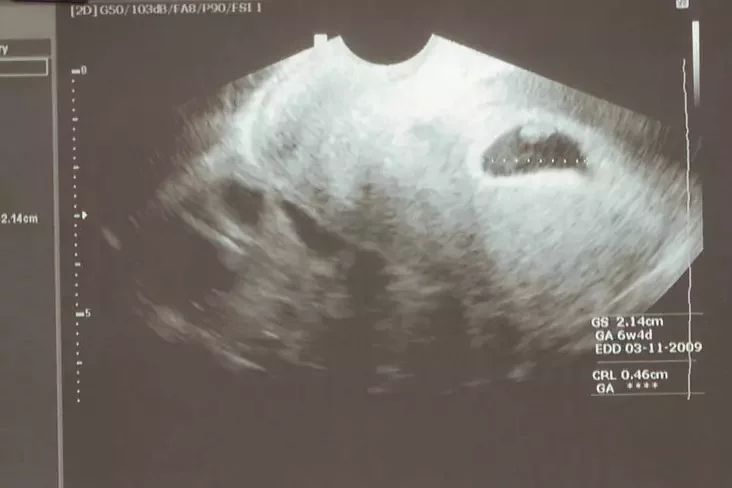

Pad čas ciažarnaści doktar budzie rehularna ahladać ciažarnuju i pryznačać praduhledžanyja dla hetaha vypadku daśledavańni, kansultacyi daktaroŭ-śpiecyjalistaŭ, a taksama analizy. Tak, ciažarnaj treba budzie prajści 3 abaviazkovyja ultrahukavyja daśledavańni płodu (UHD) — na 11—12 tydniach, na 20—22 tydniach i na 32—35 tydniach. Treba budzie zdać ahulny analiz mačy, analiz mačy pa Niečyparenku, analiz mačy na bakteryjalny pasieŭ, analiz kału, ahulny analiz kryvi + analiz kryvi na cukar (z palca), bijachimičny analiz kryvi, analiz kryvi na harmony ščytapadobnaj załozy, analiz na hrupu kryvi i Rh-faktar, analiz kryvi na sifilis, antycieły da virusaŭ hiepatytu V i S; VIČ, analiz kryvi na chłamidyi, taksapłazmoz, analiz na zhusańnie kryvi (kaahułahrama), mazok z pochvy na fłoru; pasieŭ na bakteryi, hanareju. Taksama treba budzie naviedać terapieŭta, akulista, łora, endakrynołaha, stamatołaha, zrabić kardyjahramu, UHD ščytapadobnaj załozy, a paśla 30 tydniaŭ ciažarnaści — kardyjatakahrafiju (KTH) — acenku sardečnaj dziejnaści płodu.